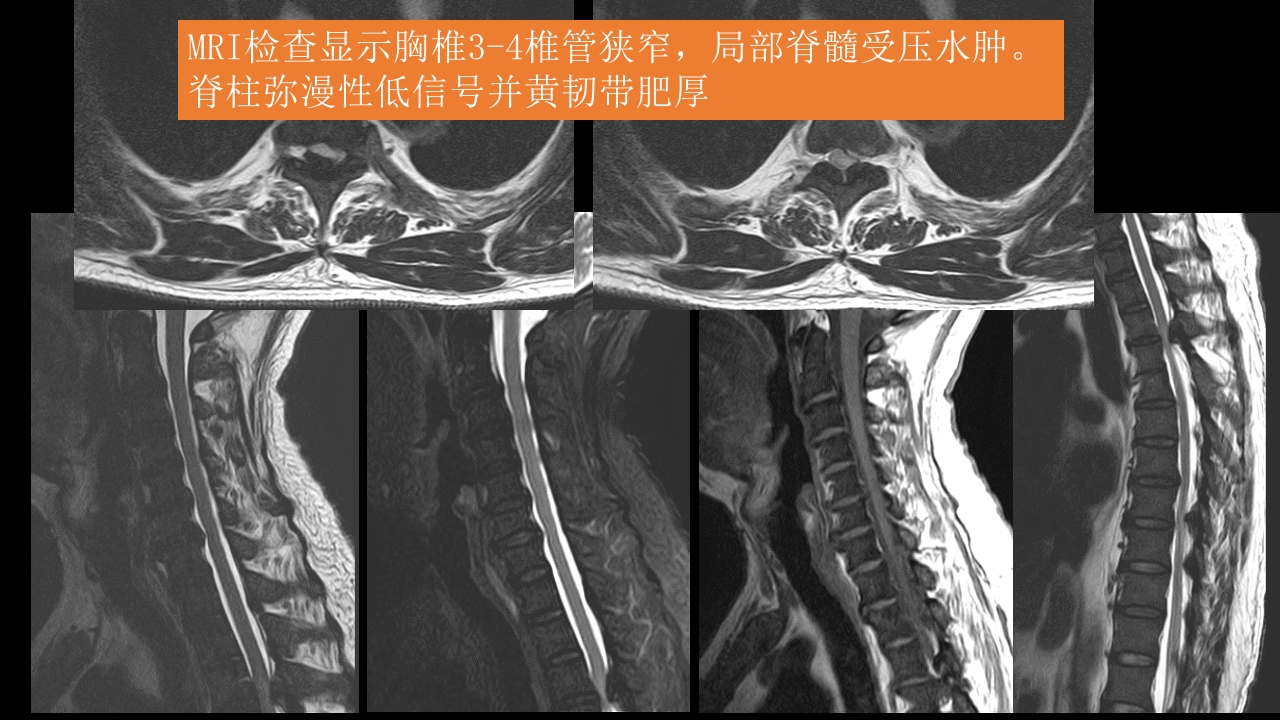

氟骨症的X线CT及MR影像及解读